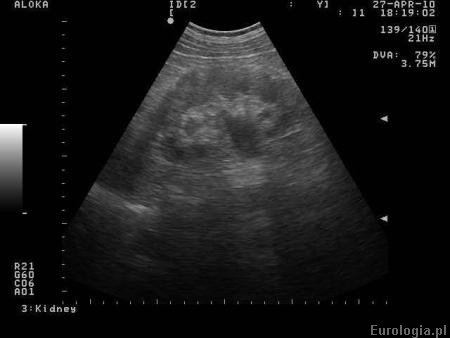

Fot. Poszerzony UKM w USG.

Poszerzone UKM u pacjenta z nadmiernie wypełnionym pęcherzem moczowym u pacjenta z pęcherzem neurogennym świadczą o wysokim ciśnieniu w pęcherzu moczowym, które powoduje utrudniony spływ moczu moczowodami lub cofanie się moczu do nerek. Sytuacja taka jest wyjątkowo niekorzystna i w przyszłości może przyczynić się do pogorszenia funkcji nerek. Zmniejszenie ciśnienia panującego w pęcherzu moczowym po mikcji spowodowało zmniejszenie zastoju w układzie kielichowo miedniczkowym - czyli łatwiejszy spływ moczu z nerki. W sytuacji przez Panią opisanej niedopuszcalne jest dopuszcanie do nadmiernego wypełnienia pęcherza moczowego.